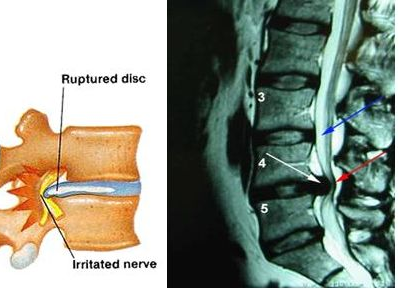

La PLDD (Discectomia Laser Percutanea) è una procedura chirurgica percutanea poco invasiva per il trattamento dell’ernia del disco. Viene eseguita nel mondo da oltre 30 anni e svariate migliaia di pazienti sono già stati operati con tale procedura. Negli ultimi anni sono inoltre stati costruiti ed utilizzati Laser chirurgici ancora più precisi e sicuri, che rendono la procedura pressoché priva di rischi, purché eseguita in strutture ospedalizzate e da specialisti della colonna vertebrale.

Numerosi lavori scientifici internazionali evidenziano una percentuale di successo intorno al 80%, con una percentuale di recidiva pari al 3% circa ed una assenza di formazione di cicatrice periradicolo-durale. In caso di insuccesso è possibile sia ripetere la procedura che ricorrere alla chirurgia senza alcuna compromissione.